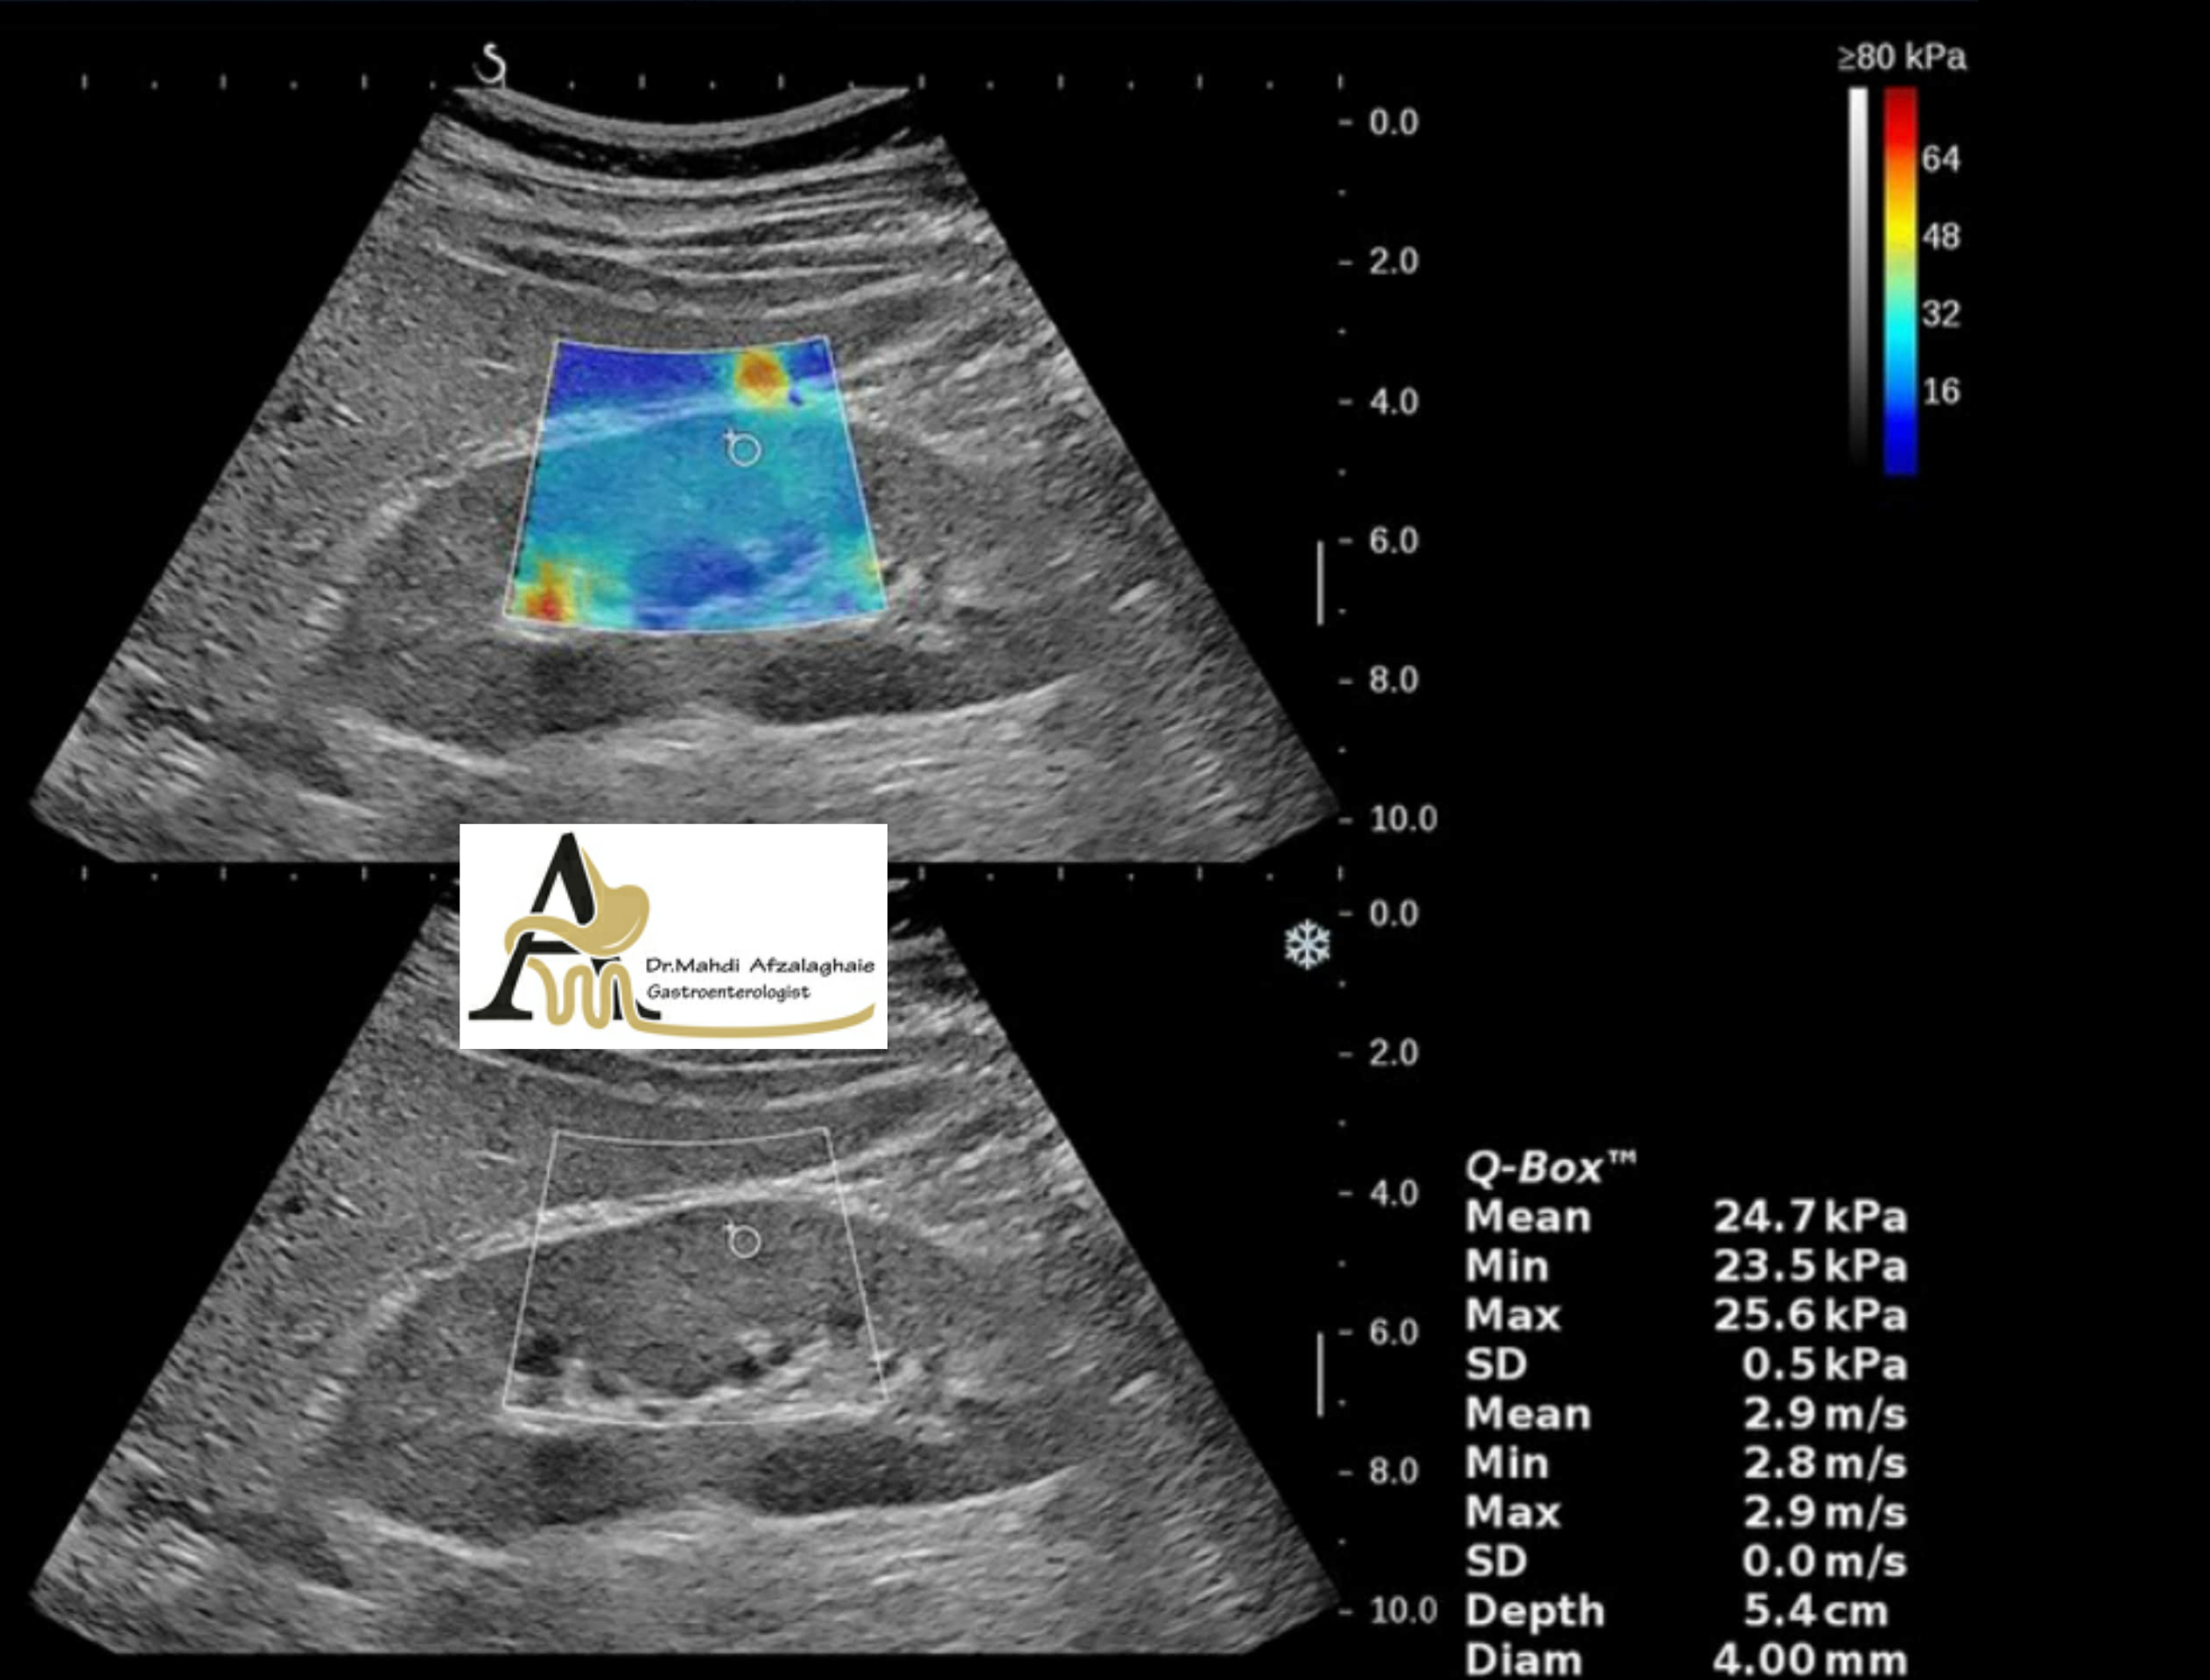

Liver elastography - gastroenterologist in Mashhad Dr. Mehdi Afzal Aghaei

One of the ways to diagnose the disease, both in the past and now, is to check the stiffness of the body par...